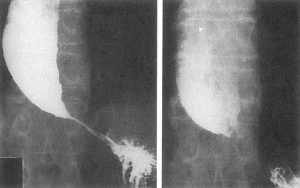

Investigation

Medical history by the patient and clinical examination by the doctor helps in diagnosis. CBC is recommended. Esophageal manometry is done. Upper GI x-ray is advised. Upper GI endoscopy is done.